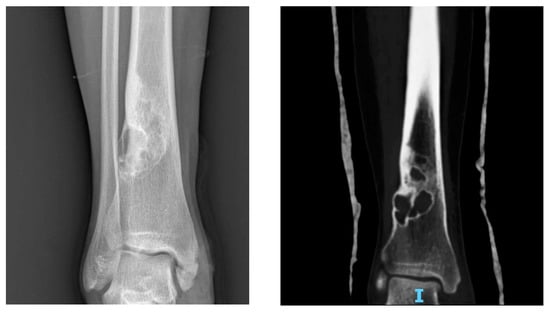

Figure 2. X-rays of multiple osteochondromas.

3.1.5. Imaging

At X-ray examination, osteochondroma is usually localized in the metaphysis, and its cortex is in continuity through a marrow cavity with the originating bone cortex. In the case of symptomatic patients, further investigations could be necessary with MRI, CT, or US. MRI is helpful to evaluate the cartilage cap and bone thickness in adults and the possible complications, such as bursae, neurological, and vascular involvement [59]. Scintigraphy shows enhancement in benign and malignant lesions; for this reason, it is not a valuable test for diagnostic purposes (Figure 2).